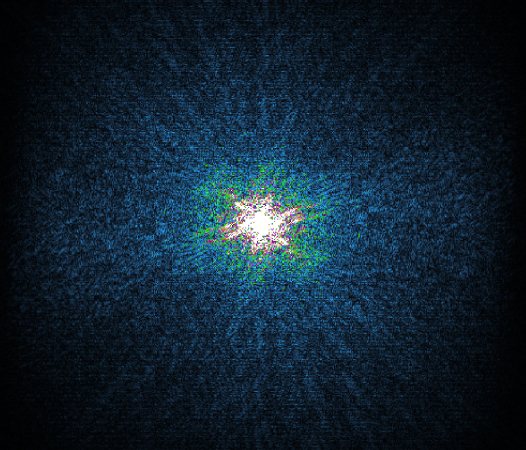

In the example below, only one fifth of the required MR radiofrequency signals is recorded. This results in a five times faster acquisition, with a subsampled k-space (top left) and inherent image artifacts after standard reconstruction (top right).

Basic compressed sensing principle

Philips Compressed SENSE

The Compressed SENSE reconstruction then uses iterative, knowledge-based algorithms to fill in the empty lines in k-space (bottom left). This removes the artifacts while keeping the final image fully consistent with the acquired data (bottom right). *Compared to Philips MR exams without Compressed SENSE